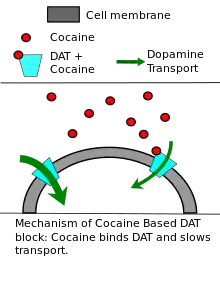

Drug addiction and psychostimulants

Cocaine, substituted amphetamines (including methamphetamine), Adderall, methylphenidate (marketed as Ritalin or Concerta), and other psychostimulants exert their effects primarily or partly by increasing dopamine levels in the brain by a variety of mechanisms.[104] Cocaine and methylphenidate are dopamine transporter blockers or reuptake inhibitors;[105] they non-competitively inhibit dopamine reuptake, resulting in increased dopamine concentrations in the synaptic cleft.[106][107]: 54–58 Like cocaine, substituted amphetamines and amphetamine also increase the concentration of dopamine in the synaptic cleft, but by different mechanisms.[37][107]: 147–150

The effects of psychostimulants include increases in heart rate, body temperature, and sweating; improvements in alertness, attention, and endurance; increases in pleasure produced by rewarding events; but at higher doses agitation, anxiety, or even loss of contact with reality.[104] Drugs in this group can have a high addiction potential, due to their activating effects on the dopamine-mediated reward system in the brain.[104] However some can also be useful, at lower doses, for treating attention deficit hyperactivity disorder (ADHD) and narcolepsy.[108][109] An important differentiating factor is the onset and duration of action.[104] Cocaine can take effect in seconds if it is injected or inhaled in free base form; the effects last from 5 to 90 minutes.[110] This rapid and brief action makes its effects easily perceived and consequently gives it high addiction potential.[104] Methylphenidate taken in pill form, in contrast, can take two hours to reach peak levels in the bloodstream,[108] and depending on formulation the effects can last for up to 12 hours.[111] These longer acting formulations have the benefit of reducing the potential for abuse, and improving adherence for treatment by using more convenient dosage regimens.[112]

A variety of addictive drugs produce an increase in reward-related dopamine activity.[104] Stimulants such as nicotine, cocaine and methamphetamine promote increased levels of dopamine which appear to be the primary factor in causing addiction. For other addictive drugs such as the opioid heroin, the increased levels of dopamine in the reward system may play only a minor role in addiction.[113] When people addicted to stimulants go through withdrawal, they do not experience the physical suffering associated with alcohol withdrawal or withdrawal from opiates; instead they experience craving, an intense desire for the drug characterized by irritability, restlessness, and other arousal symptoms,[114] brought about by psychological dependence.

The dopamine system plays a crucial role in several aspects of addiction. At the earliest stage, genetic differences that alter the expression of dopamine receptors in the brain can predict whether a person will find stimulants appealing or aversive.[115] Consumption of stimulants produces increases in brain dopamine levels that last from minutes to hours.[104] Finally, the chronic elevation in dopamine that comes with repetitive high-dose stimulant consumption triggers a wide-ranging set of structural changes in the brain that are responsible for the behavioral abnormalities which characterize an addiction.[116] Treatment of stimulant addiction is very difficult, because even if consumption ceases, the craving that comes with psychological withdrawal does not.[114] Even when the craving seems to be extinct, it may re-emerge when faced with stimuli that are associated with the drug, such as friends, locations and situations.[114] Association networks in the brain are greatly interlinked.[117]